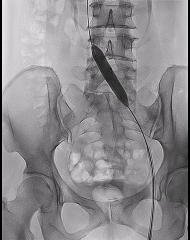

2、导管导丝配合通过病变段后建立导丝路径,依次选择Atlas Gold 12*60mm、Atlas Gold 14*60mm对髂静脉逐段逐级扩张,扩张过程中见明显切迹。

3、扩张结束后,送入Venovo髂股静脉支架 14*120mm,先大滚轮缓慢释放,便于支架近心端的定位,避免过多进入下腔静脉,遮挡对侧髂静脉开口。当近心段充分锚定后,通过小滚轮将整个支架进行完整的释放。

4、再次造影,支架形态良好,髂静脉狭窄解除,髂静脉回流较术前明显改善,髂内静脉返流消失,周围侧支减少。